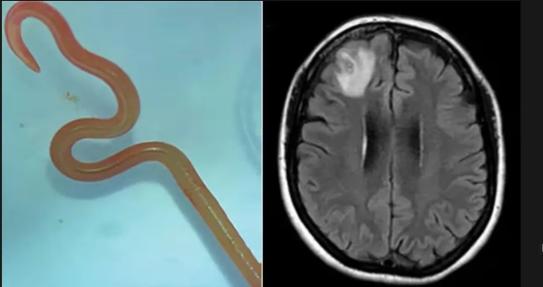

全球出现首例蛇蛔虫感染者近日,澳大利亚新南威尔士州出现了全球首例蛇蛔虫感染者。患者因为发烧、健忘等症状就诊后,医生发现该患者大脑核磁共振扫描显示出异常情况,并从其大脑中取出了一条长达8厘米且还在蠕动的蛇蛔虫。这种寄生虫是一种常见于蟒蛇体内的蛔虫,该患者是世界上感染此类寄生虫的首例病例。